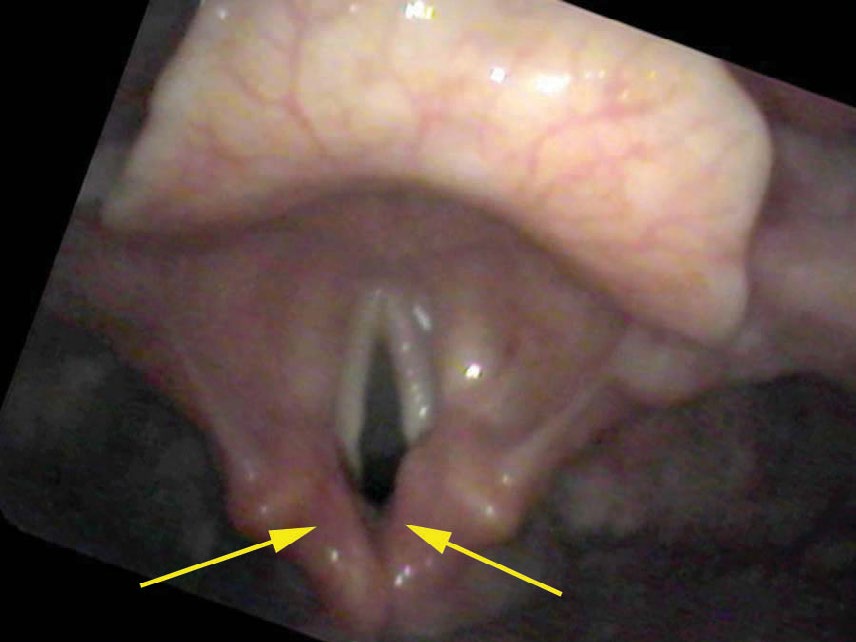

When I place the endoscope through her nose and begin to view her larynx, the larynx appears with a reddish hue. This is the view obtained by the typical otolaryngologist who examines the vocal cords from five or more centimeters away. Many physicians tend to focus on the back of the larynx and state that the “interarytenoid area is red, so it must be reflux.” Since I have never seen reflux laryngitis, I move the endoscope extremely close to her vocal cords.

If we stop and search this close-up view for a time, we will begin to perceive that all of the vessels dim in the central portion of the vocal cord. They are actually diving under a thin film of white. Because the vocal cord itself is white, a white film on the surface (white on white) is not easily discernible. But if we concentrate on the vessels, we can see a distinct curving line where the vessels fade or disappear as they traverse the central portion of the vocal cord.

I make a diagnosis of fungal laryngitis since I perceive a whiteness and the typical throat fungus is Candida albicans, which is white. Fungus growing on the vocal cords would also stimulate increased blood flow or inflammation. The patient is on a steroid spray that, while very good for the prevention of asthma, will encourage the overgrowth of the normal fungal flora in the mouth and throat (also known as thrush).

- The key finding is a thin white film on the surface of the vocal cords that partially obscures the blood vessels beneath — visible only on very close inspection, often within one millimeter of the cord.